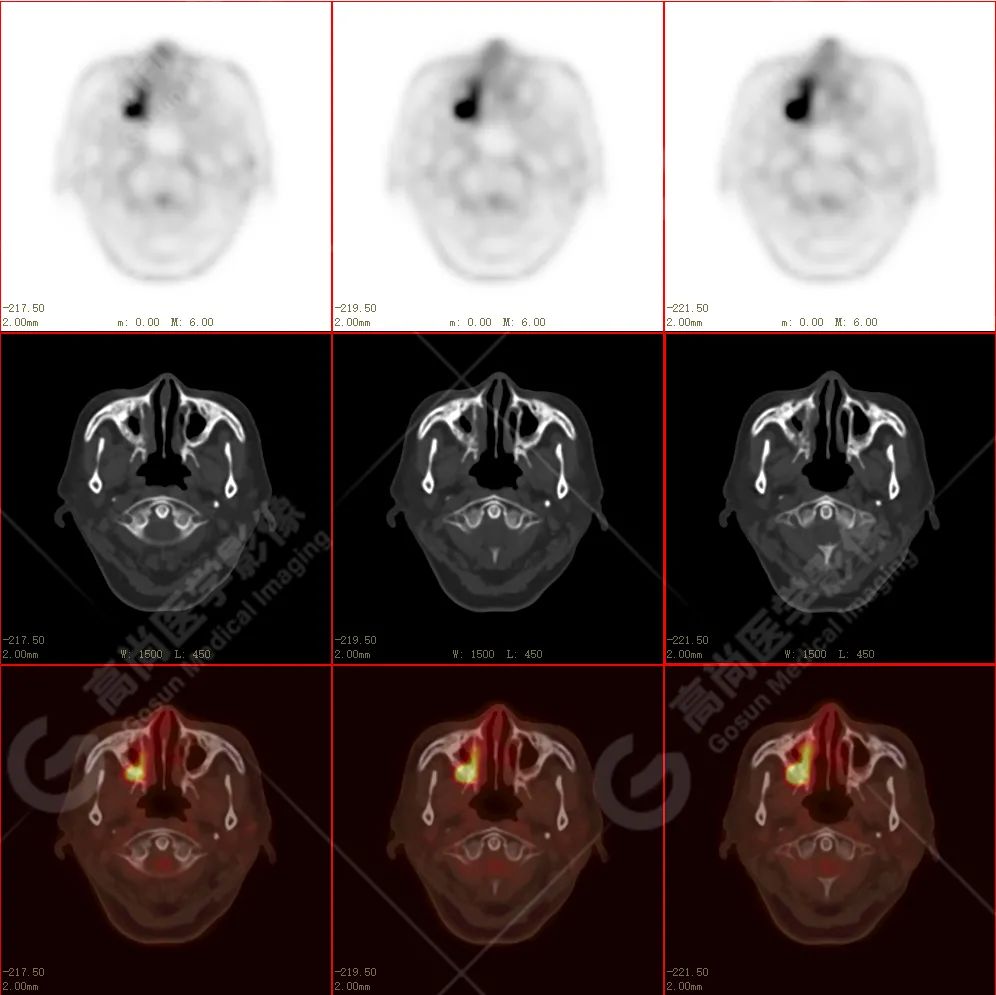

右侧上颌骨-上颌窦骨壁-骨性鼻中隔区域见片块状放射性摄取异常增高影,最大层面约 4.1 cm×3.8 cm×2.8 cm,SUV 最大值为 10.4,CT 示上述部位见成骨性改变,骨质不均匀弥漫性增厚、密度不均匀增高,并可见肿瘤骨影,边缘毛糙,周围伴软组织增厚。

根治性手术在放疗后骨肉瘤的治疗中是必须的,然而根治性手术仅仅适用于早期的病例,如本例病人,相对早期,周围组织结构无明显侵犯,PET 示肿瘤代谢也局限于肿瘤本体。